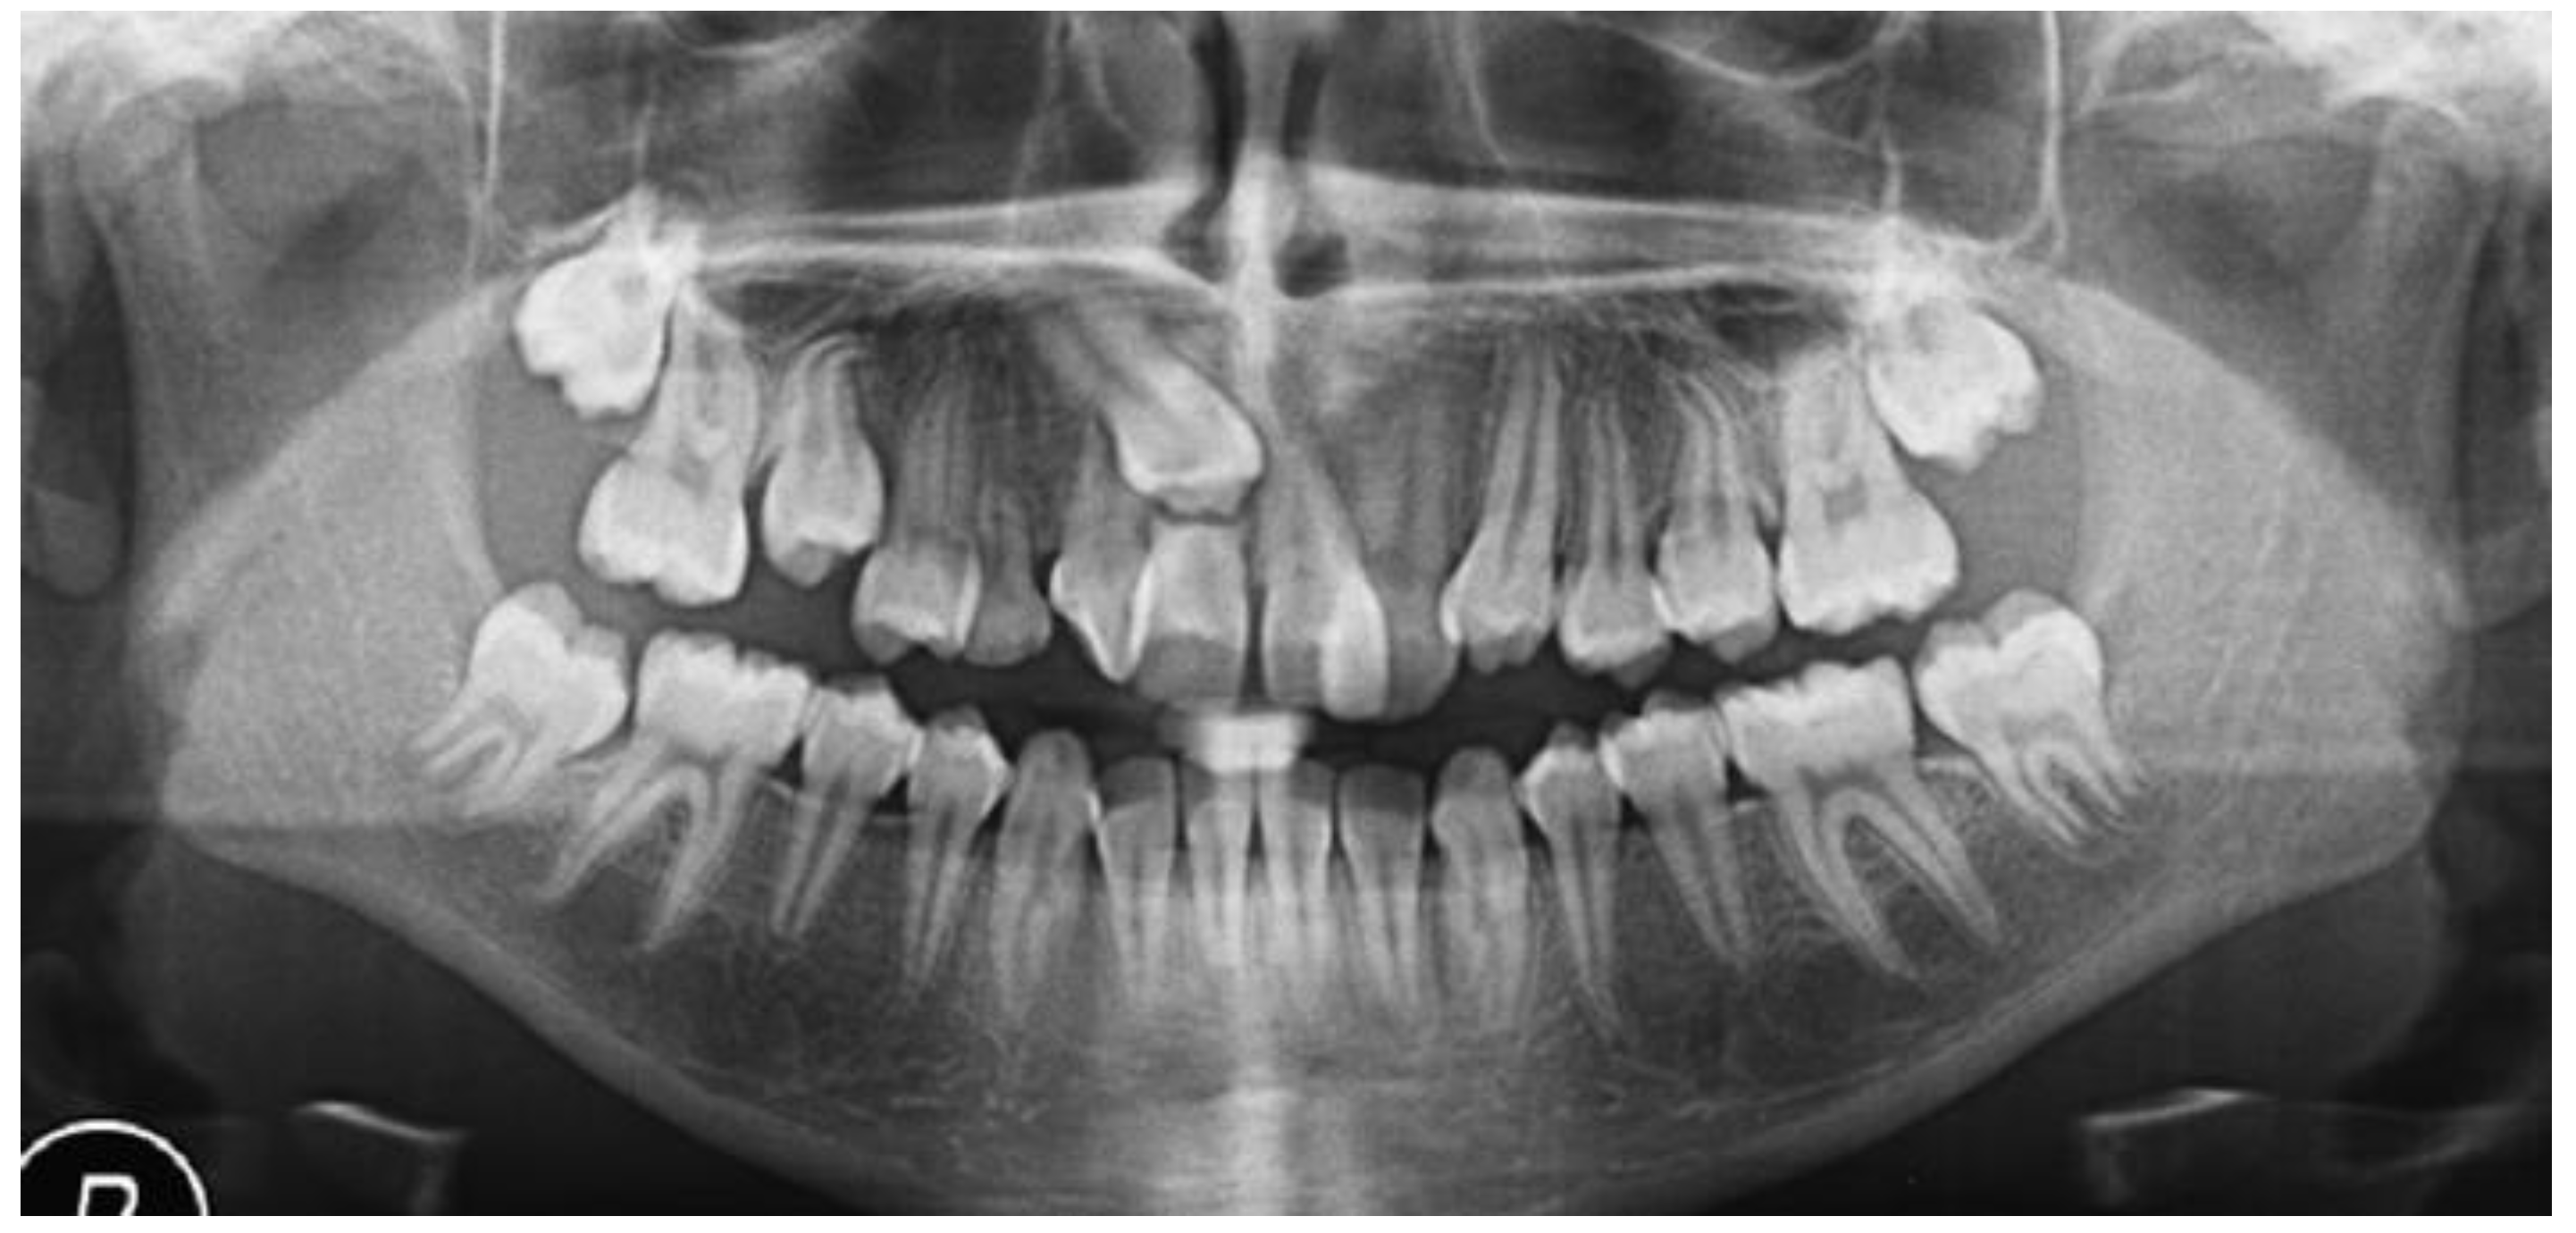

2.7. Clinical Case

| Pinho T., Amaral R. 2025 | ♀ 13 YO | Mx.C.I1 | C | R | V (impacted) | Cl I | Maintained | -Total root resorption of tooth #11 due to the position of the ectopic canine |

3.2. Clinical Case